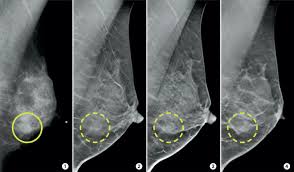

Tumors may be benign or cancerous. According to the american cancer society (acs), the most common sign of breast cancer is a new lump or mass in the breast. Most people assume that what doctors are looking for on a mammogram are lumps, dr. It can be hard to know from a mammogram image whether the cluster is dcis or invasive breast cancer. Testing for breast cancer tumor markers depends on the different stages of the cancer.

The first stage of breast cancer detection is the mammogram, ultrasound or breast magnetic resonance imaging exam, all of which are sensitive enough to detect breast cancer before any symptoms are noticeable.if there are any suspicious signs, then a biopsy is carried out, and only then are tests for breast. It is also an anatomic test, which means cancer is detected based on changes in how the breast anatomy looks. Fluid is black on an ultrasound. The most common sign of breast cancer is a lump, deep in the breast. Mammograms may show suspicious areas of the breast, white spots, and microcalcifications. Ultrasounds are useful for detecting signs of breast cancer even after a mammogram comes back negative. Your doctor will note if they have changed over time. • microcalcifications are small and may appear in clusters. Lobular carcinoma) are more difficult to detect than. It can be hard to know from a mammogram image whether the cluster is dcis or invasive breast cancer. You can tell they are solid due to their grey color. Tumors may be benign or cancerous. Rather than an image that is formed from pictures taken from top to bottom and side to side like a.

Mammogram Images Understanding Your Results from images-prod.healthline.com They are not usually related to cancer. It can be hard to know from a mammogram image whether the cluster is dcis or invasive breast cancer. That's only half the story.. This type of cancer also changes the appearance of your breasts. How can mammograms be used? What does breast cancer look like on a mammogram? A lump is not always easy to feel. This may include normal tissue and glands, as well as areas of benign breast changes (e.g., fibroadenomas) and disease (breast cancer).

While it is useful to know what cysts and tumors look like in an ultrasound image, always rely on the insight of an experienced doctor or radiologist when. The look of breast cancer on a mammogram a tumor or lump will appear as a focused white area on the mammogram. The photographs included on this page are the results of reconstructive procedures performed by the surgeons at the center for restorative breast surgery. Any area that does not look like normal tissue is a possible cause for concern. A mammogram can show breast changes such as calcifications, masses, or other symptoms that might be cancer. During a breast exam, your doctor looks for visual changes and uses their fingers to feel for lumps. They are usually benign (not cancer). Inflammatory breast cancer affects breast tissue and can appear unusually dimpled or thick. • microcalcifications are small and may appear in clusters. Dulce corazon the transfer of estrogen from a mother to her newborn child may cause breast lesions on the child. Most people assume that what doctors are looking for on a mammogram are lumps, dr. The doctor reading your mammogram will be looking for different types of breast changes, such as small white spots called calcifications, larger abnormal areas called masses, and other suspicious areas that could be signs of cancer. The following images show what cancer looks like on an ultrasound.

Tmist Trial Comparing Breast Cancer Screening Approaches National Cancer Institute from www.cancer.gov These deposits show up as tiny white spots on a mammogram, and there may be only one or two, or too many to count, says jay baker, md, a breast imaging specialist at the duke cancer center. It is also an anatomic test, which means cancer is detected based on changes in how the breast anatomy looks. You may have an imaging test, like a mammogram or ultrasound, for an inside look. A lump is not always easy to feel. Fluid is black on an ultrasound. Dulce corazon the transfer of estrogen from a mother to her newborn child may cause breast lesions on the child. A screening mammogram is performed at regular intervals to check for breast cancer in women who have no signs or symptoms of the disease. Breast cancer can appear as a spiculated mass, cluster of tiny calcifications, smoothly marginated mass, area of subtle distortion or be invisible on.